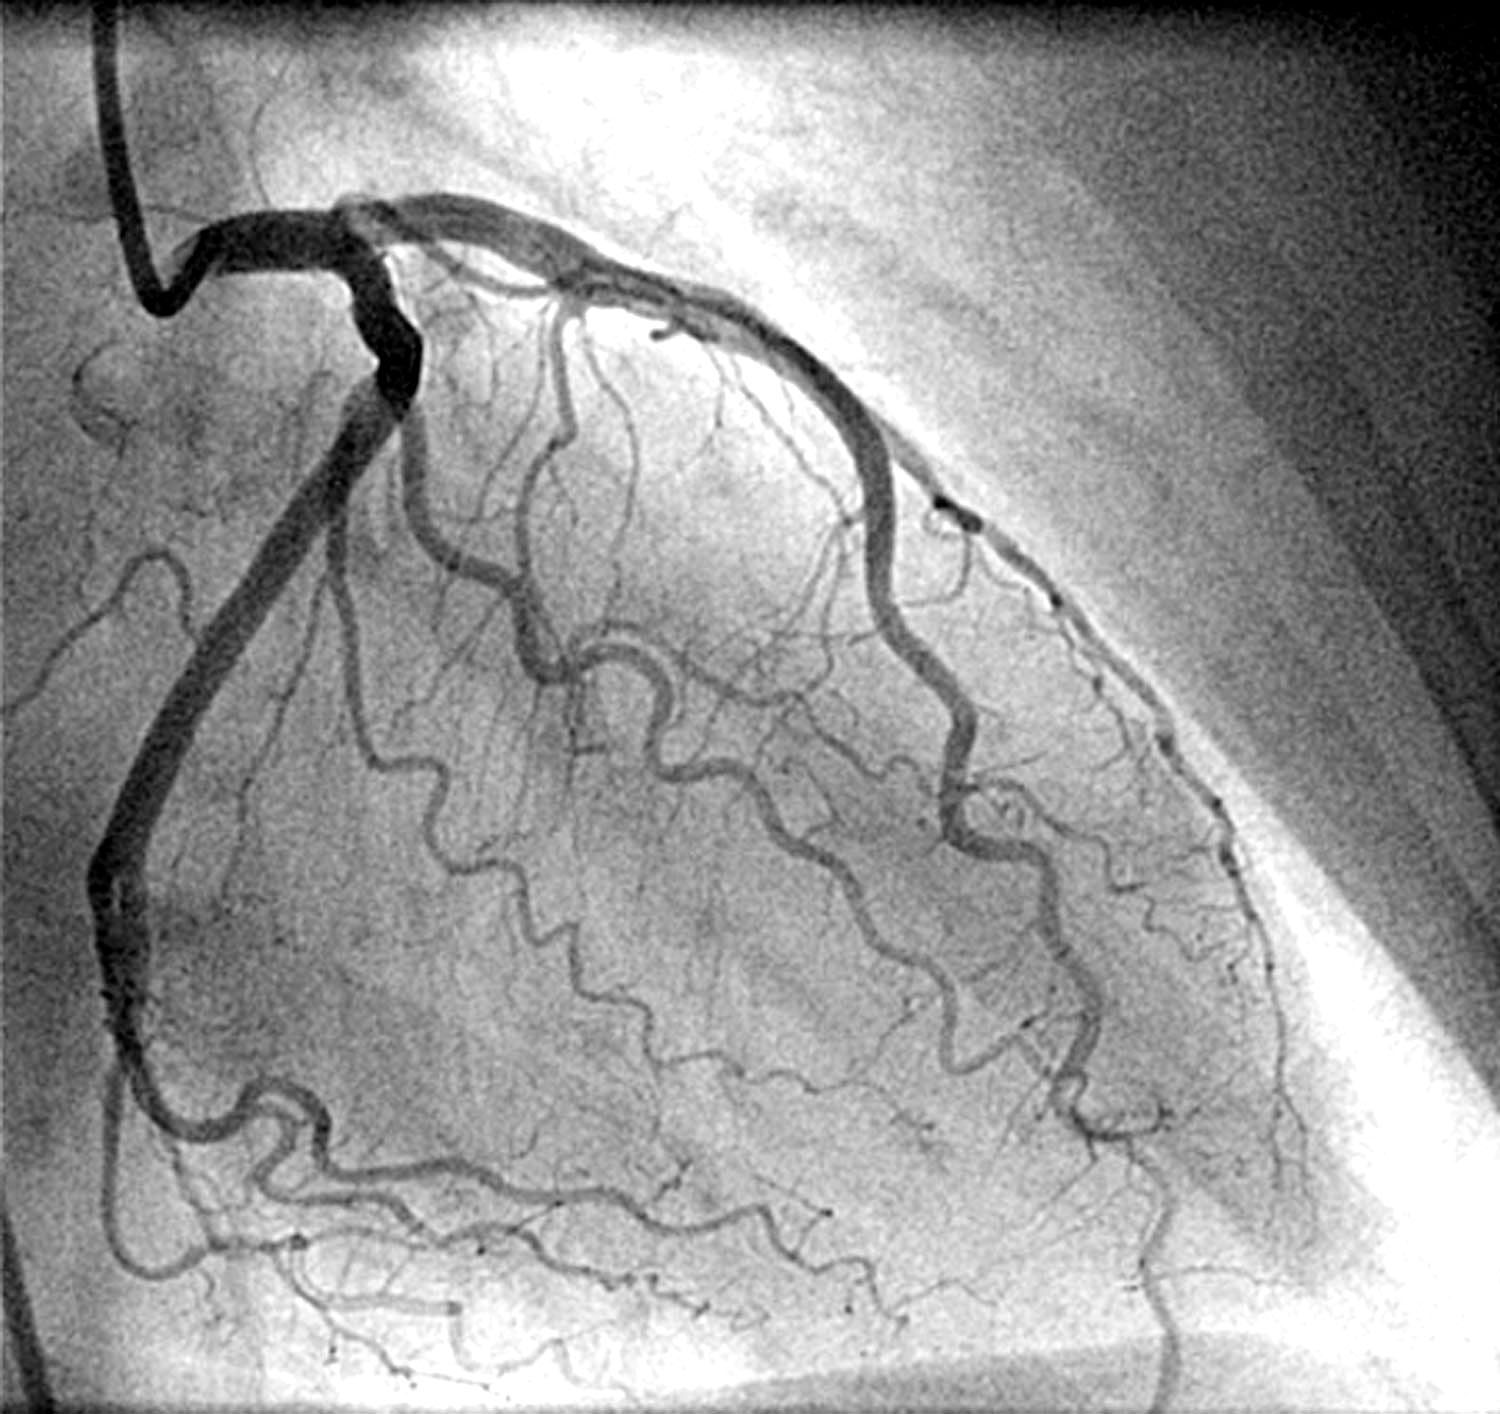

1. SBS delle arterie coronarie

- Angina pectoris

- Attivazione: Perdita di territorio maschile o frustrazione sessuale femminile (in relazione a sesso, lateralità, conflitti precedenti, situazione ormonale ed età). La perdita del territorio maschile comporta la perdita dell'intero territorio o di qualcosa in esso contenuto. Ad esempio, qualcuno perde il proprio partner, il proprio lavoro o il proprio grado. Qualcuno perde la propria casa, la propria attività o i propri soldi. «Mi ha spezzato il cuore!»

Per la perdita del territorio maschile si tratta del "territorio esterno", al femminile del "territorio interno". - Foglietto embrionale: Ectoderma.

- Conflitto attivo: Perdita cellulare (ulcera) del tessuto epiteliale dotato di terminazioni sensoriali sulle superfici lisce delle arterie coronarie (intima delle arterie coronarie). Questo "allargamento" dei vasi è difficilmente diagnosticata, poiché la Religione Medica cerca solo restringimenti, non un aumento della sezione arteriosa. Angina pectoris.

- Senso biologico: A causa della perdita cellulare, il lume delle arterie coronarie si allarga: migliore apporto di sangue al cuore e maggiore capacità del cuore di poter recuperare nuovamente il territorio e/o il suo contenuto.

- Fase di riparazione: Ricostruzione del tessuto epiteliale delle arterie coronarie. Restringimento (stenosi) delle arterie coronarie dovuto al gonfiore durante la guarigione (malattia coronarica o aterosclerosi). Possibile valore alto del colesterolo LDL.

- Crisi epilettoide: Attacco cardiaco, da 2 a 6 settimane dopo l'inizio della fase di riparazione.